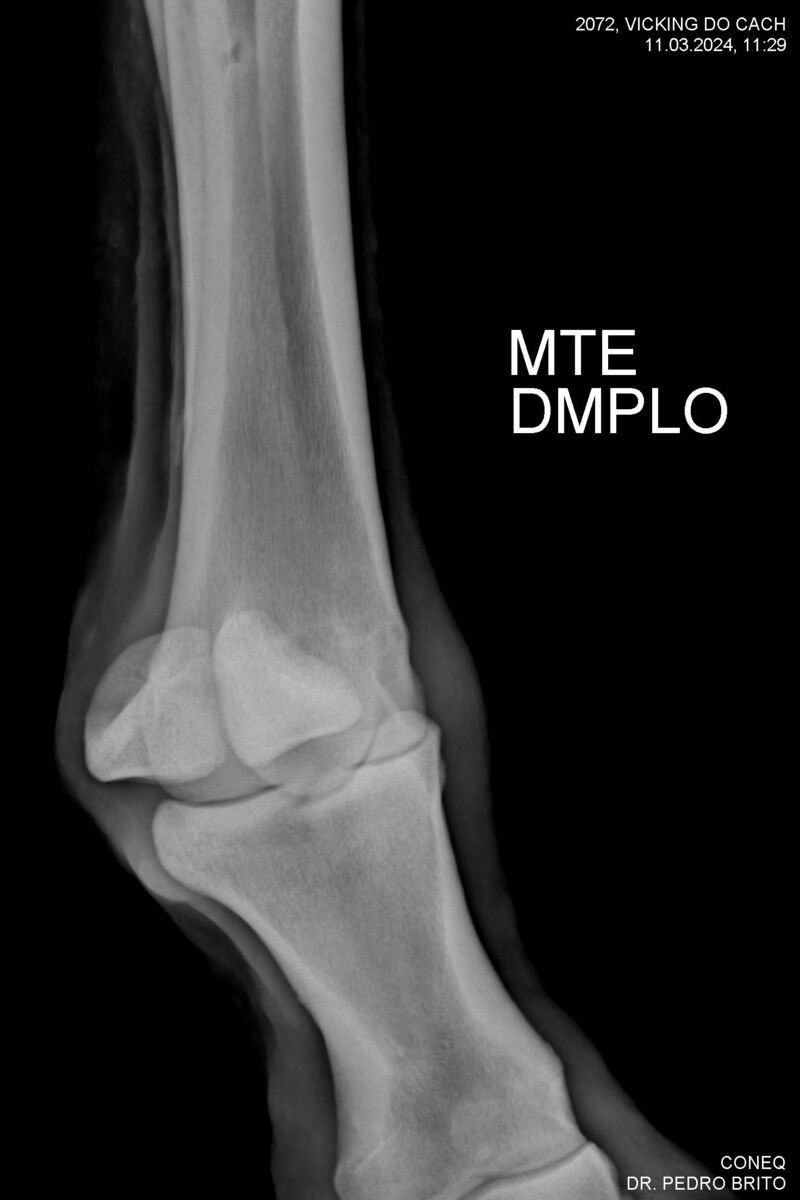

VIKING DO CACH